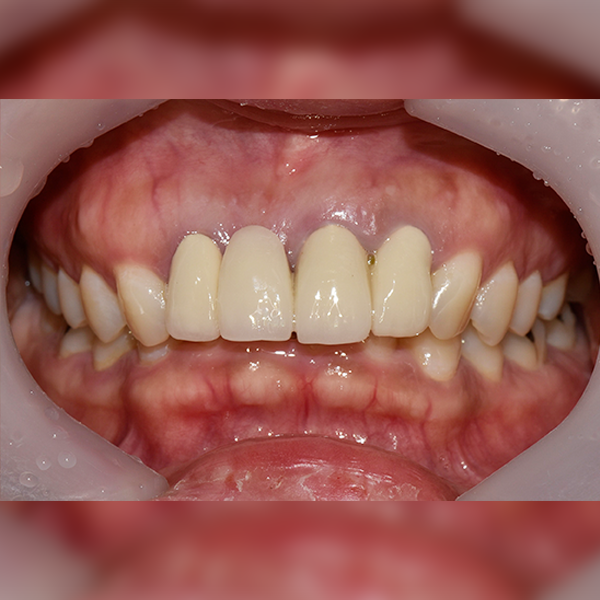

3. 症例.111 30代 趙*善 2018-11-30 / 2019-12-10

上顎 / 前歯部 / 3本以下 / 骨移植

症例.111 30代 趙*善 2018-11-30 / 2019-12-10

After After

Before Before